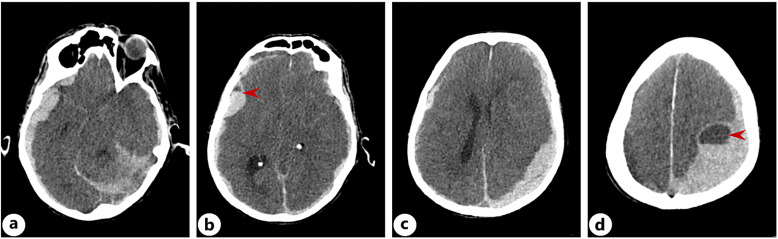

Case presentation: We present 5 patients who received pembrolizumab as a part of their treatment. They exhibited a variety of clinical manifestations, which included central nervous system involvement and necrotizing myopathy, each responding differently to therapeutic interventions. Among the participants, there were two cases of myopathy, one case of demyelinating polyneuropathy, one individual whose myasthenia gravis had worsened, and 1 patient diagnosed with encephalitis. The patients experienced symptoms with varying degrees of severity, leading to different responses in their clinical treatment, and 1 patient ultimately passed away due to complications.